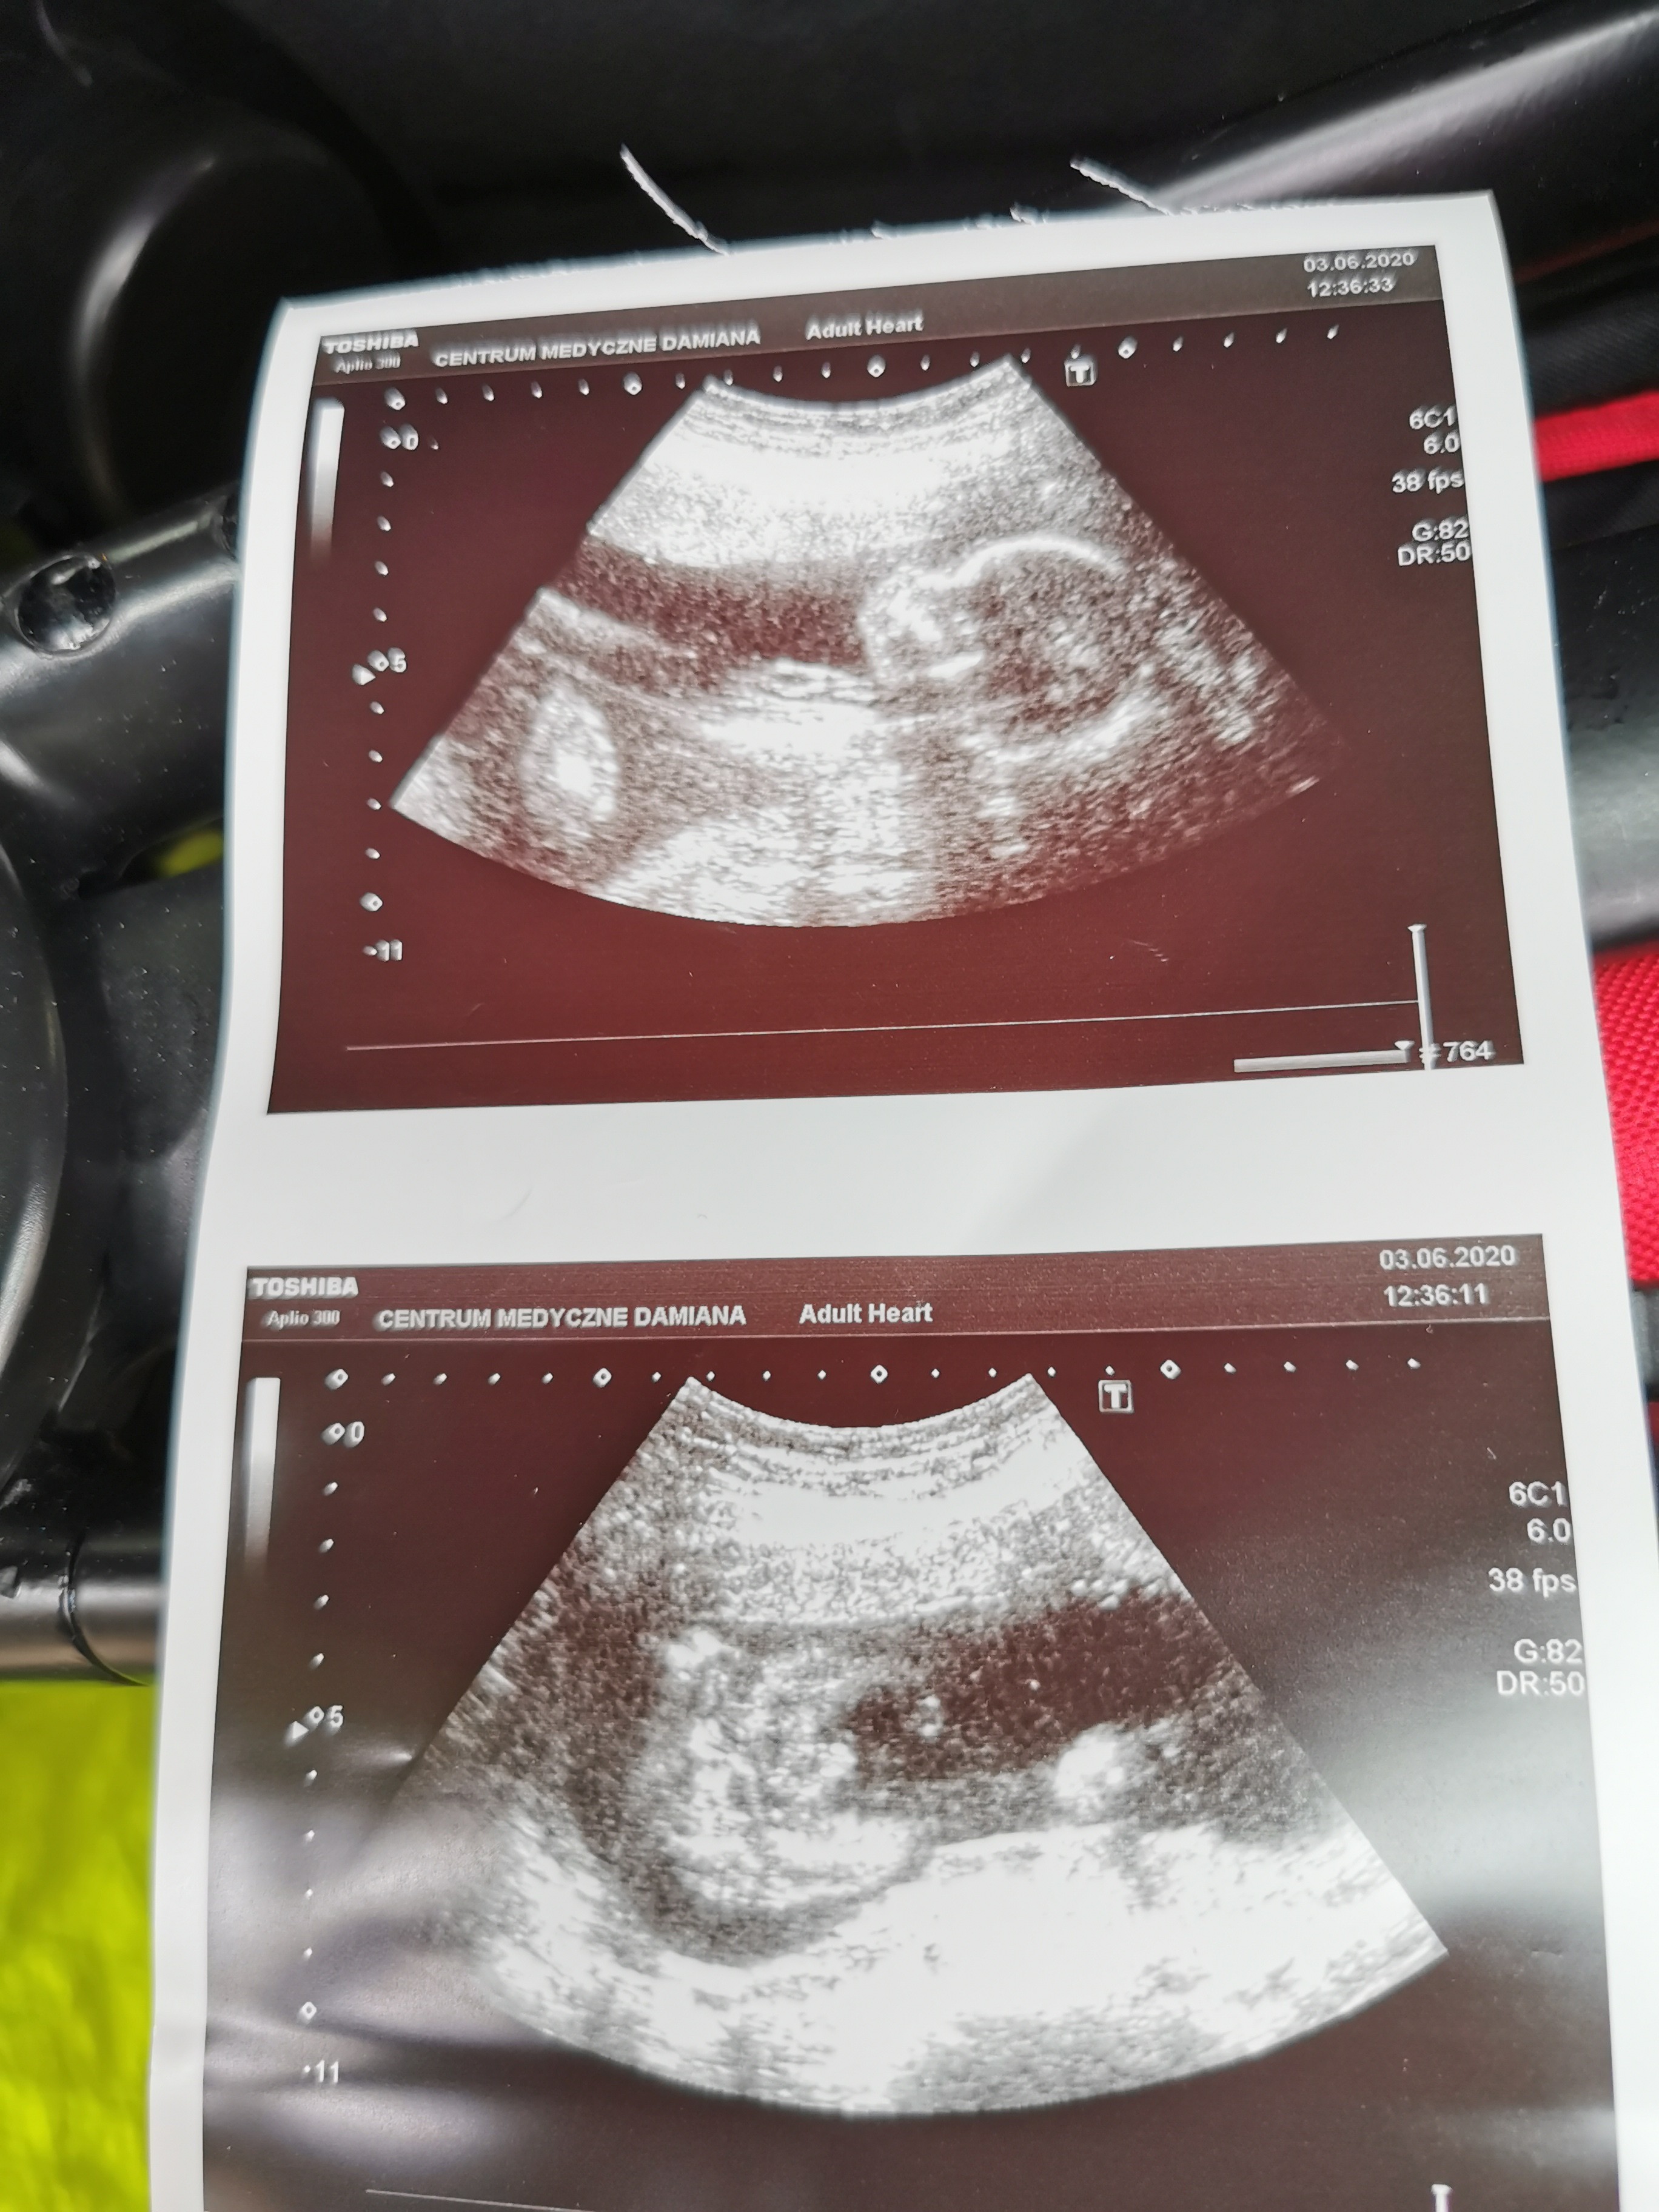

Nie dało się tylko zrobić pomiarów, ale to co na oko, to wszystko było widać, młody się nie kryje z tym, ze jesqt malym facetem, wszystko widoczne

Tygrysek urósł, serduszko ładnie bije, wszystkie czesci ciała na swoim miejscu, pomachał nam nawet, ruszał się tak fajnie

Łożysko na przedniej ścianie.

Tylko 2 zdjęcia mam, ale to akurat najmniejszy problem